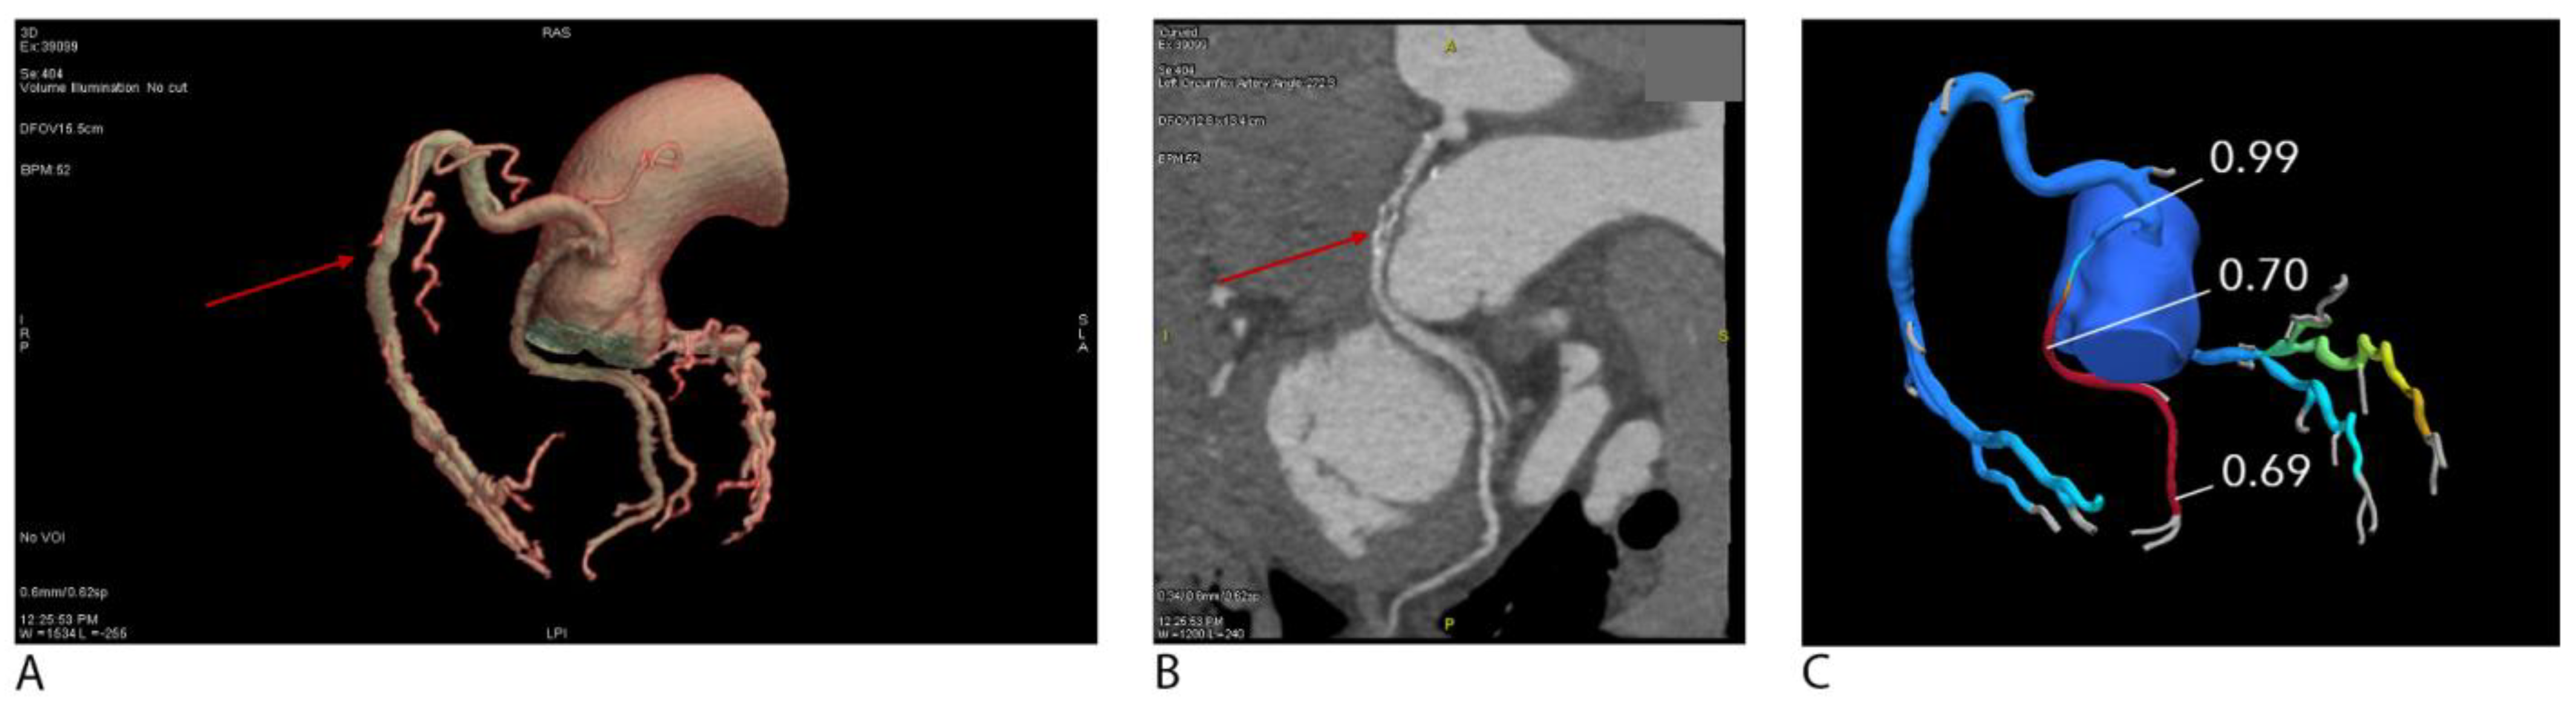

As demonstrated in Figure 3A,B, curved planar CCTA clearly visualizes a severe focal stenosis in the mid-LAD, confirmed by selective coronary angiography. This highlights CCTA’s excellent correlation with invasive gold standards.

Figure 3. (A) Curved planar reformatted coronary CT angiography (CCTA) demonstrates a severe (>70%) focal stenosis in the mid left anterior descending artery (LAD), characterized by mixed plaque with both non-calcified and calcified components, as well as eccentric calcification. The red arrow points to a severe (>70%) focal stenosis in the mid LAD. (B) Invasive coronary angiography of the same patient confirms the presence of a severe stenosis in the mid-LAD (arrow).